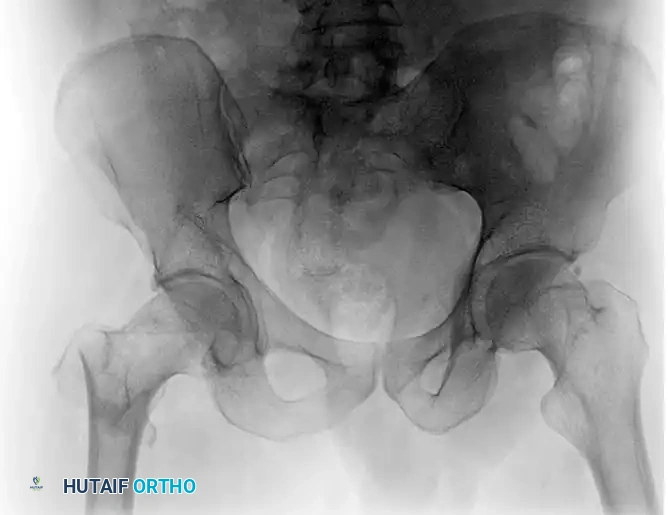

Intertrochanteric femoral fractures represent a significant proportion of fragility fractures encountered in orthopedic trauma. The primary goal of surgical intervention is to achieve stable fixation that permits early mobilization, thereby mitigating the profound morbidity and mortality associated with prolonged recumbency in the geriatric population.

Understanding fracture morphology is paramount when selecting the appropriate implant. Intertrochanteric fractures are broadly categorized into stable and unstable patterns based on the integrity of the posteromedial cortex (calcar femorale) and the lateral trochanteric wall.